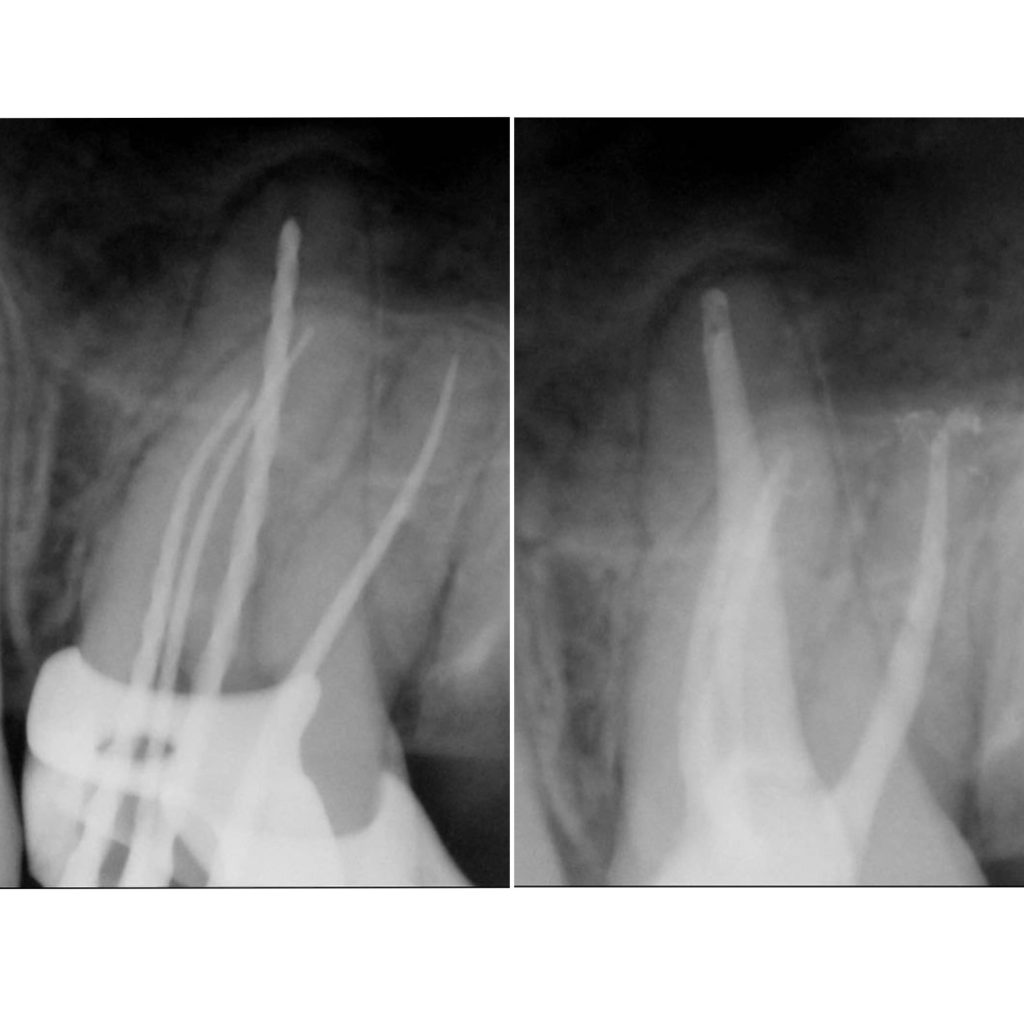

• Эндодонтическое лечение корневых каналов с использованием стоматологического микроскопа

2022 год – «Первичная эндодонтия с использованием современных клинических протоколов» Андрей Кольба

2023 год – «Первичная эндодонтия» Виталий Весна

2025 год – «Современные протоколы лечения эндодонтических пациентов» Dental Education Clinic,курс Елены

Драган